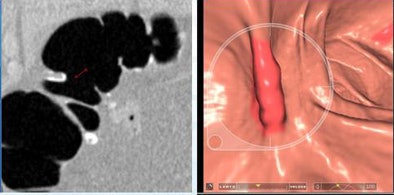

| Six lesions located on haustral folds showed higher conspicuity in 3D versus 2D renderings. In particular, focal thickening and surface irregularities were more visible at 3D. All images courtesy of Dr. Franco Iafrate. |

Six polyps located on the haustral fold showed higher conspicuity on the 3D endoluminal view than on the 2D view (colon window setting), Iafrate said.